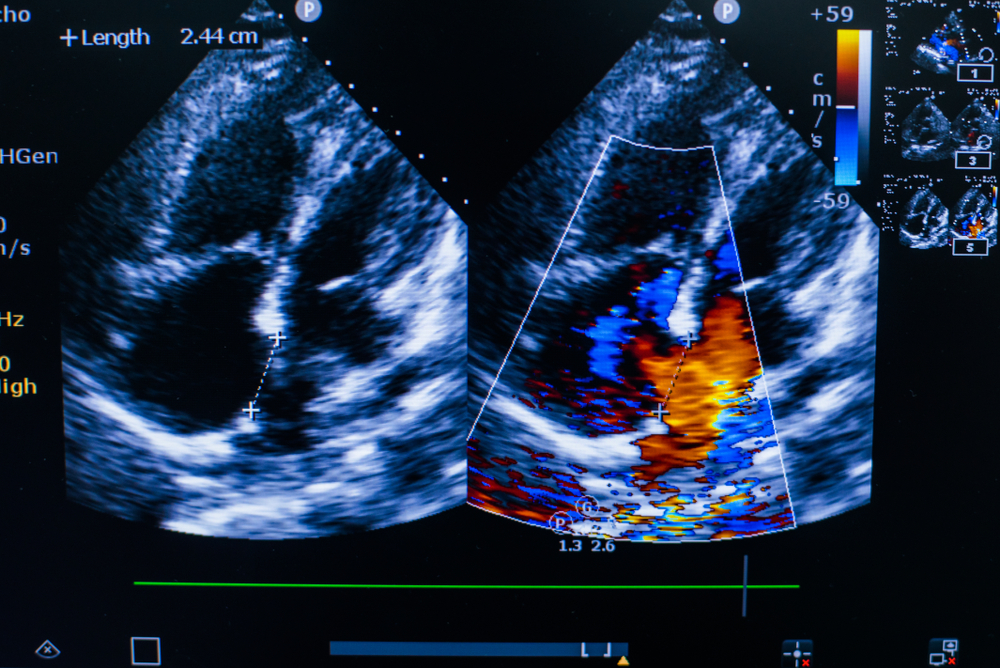

L’échographie cardiaque, ou échocardiographie, est un examen d’imagerie médicale qui utilise les ultrasons pour observer le cœur en mouvement. Indolore et sans danger, il permet d’évaluer la structure du cœur, son fonctionnement et ses valves. C’est un outil essentiel pour diagnostiquer certaines maladies cardiaques et surveiller l’état du muscle cardiaque.

- Analyser le fonctionnement des valves cardiaques

- Détecter une anomalie, comme un rétrécissement ou une fuite valvulaire